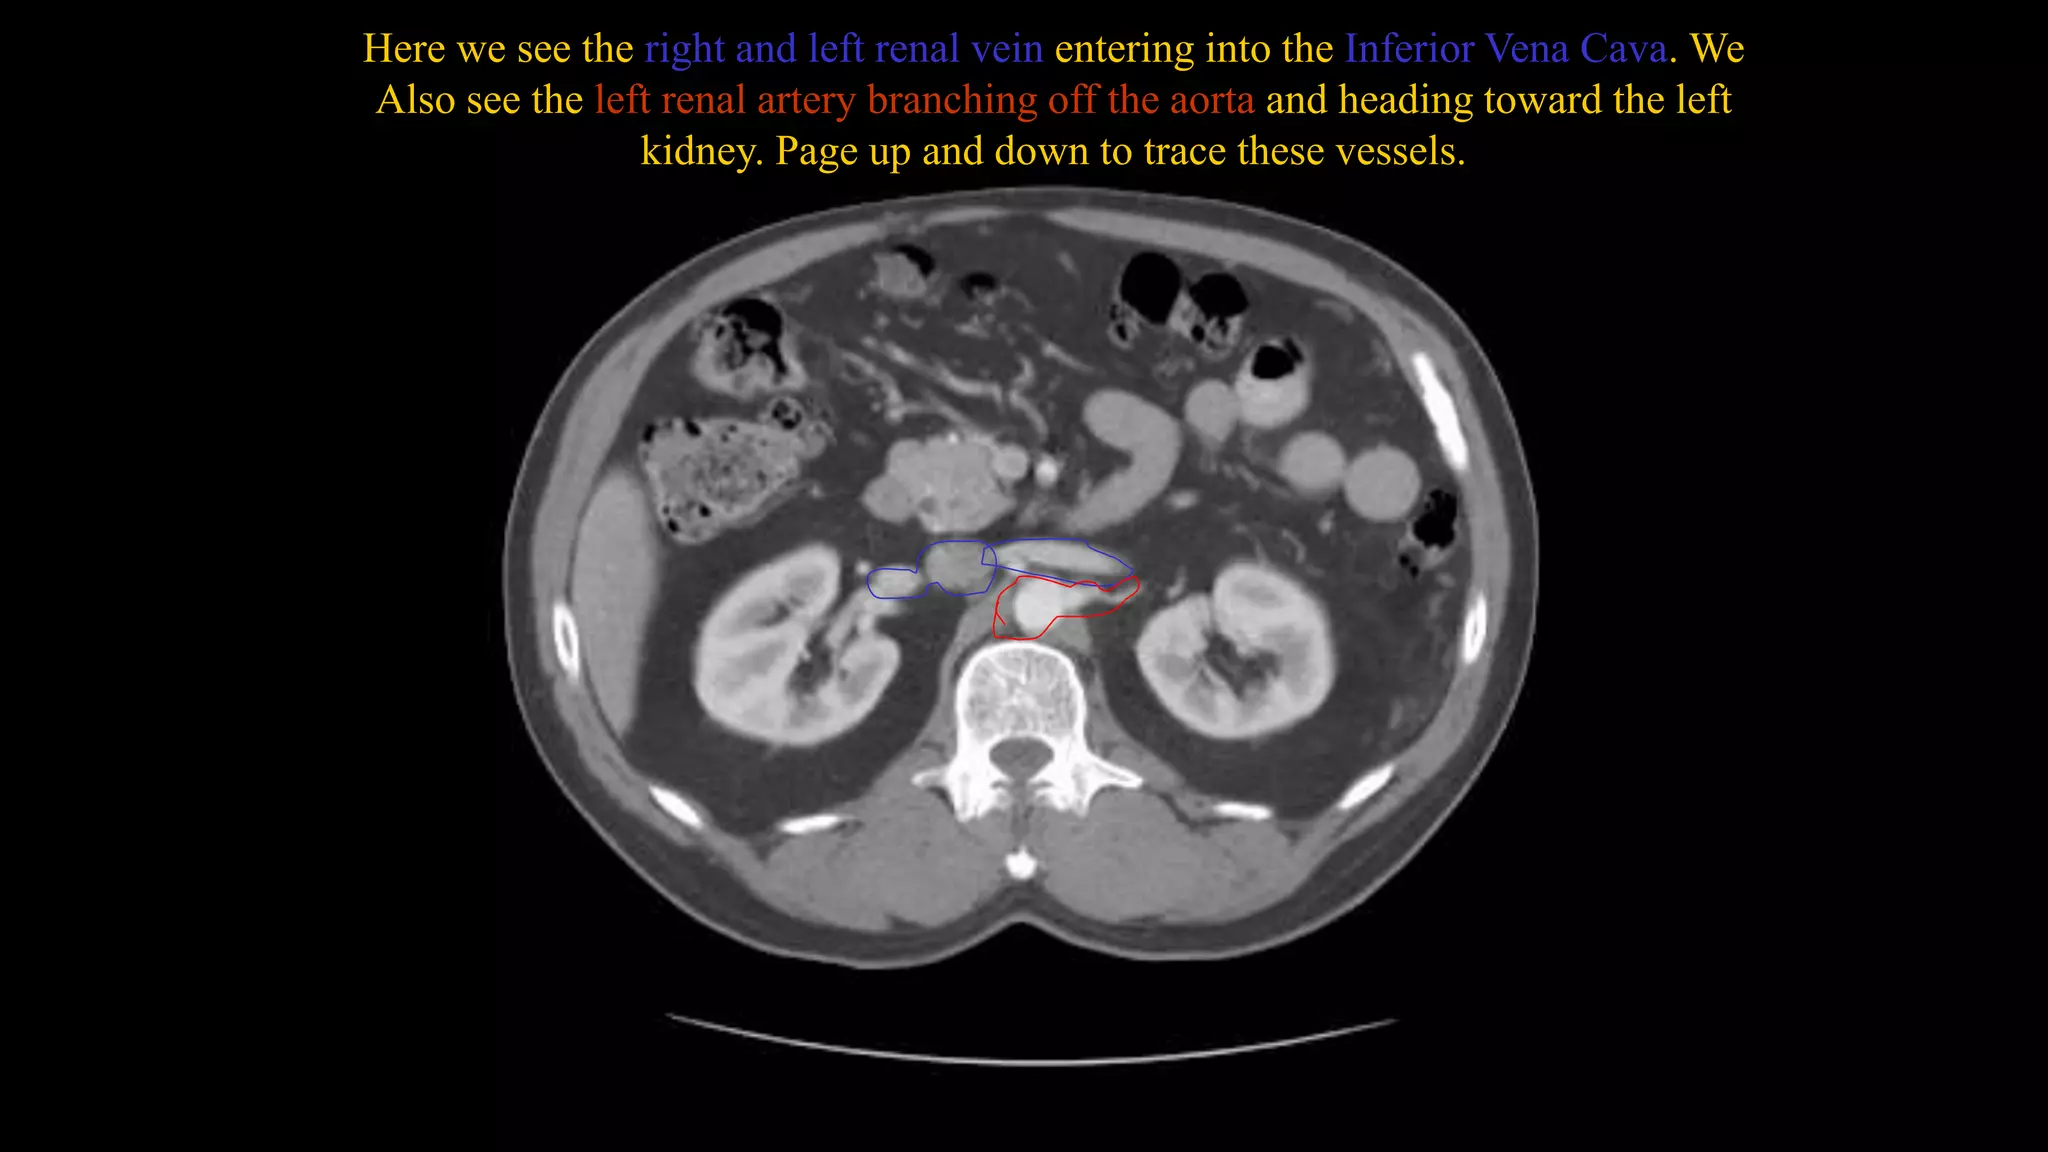

Here we see the right and left renal vein entering into the Inferior Vena Cava. We

Also see the left renal artery branching off the aorta and heading toward the left

kidney. Page up and down to trace these vessels.